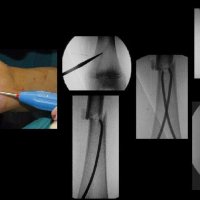

TITANIUM ELASTIC NAILING (TEN)

Titanium Elastic Nailing (TEN) is intended for fixation of diaphyseal fractures of long bones where the medullary canal is narrow or flexibility of the implant is paramount. The biomechanical principal of the Titanium elastic nailing is based on the symmetrical bracing action of two elastic nails inserted into the metaphysis, each of which bears against the inner bone at three points. The complication rates associated with Titanium elastic nailing have been reported to be minimal.